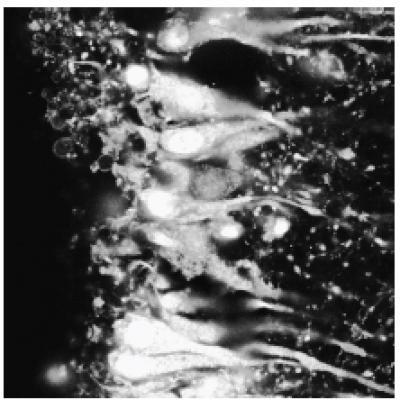

This is an image of a rat brain slice loaded with the Arg-Cy3-TIVA tag. Loading of the cells is apparent from the white fluorescence.

(Photo Credit: James Eberwine, Ph.D., Perelman School of Medicine, University of Pennsylvania)